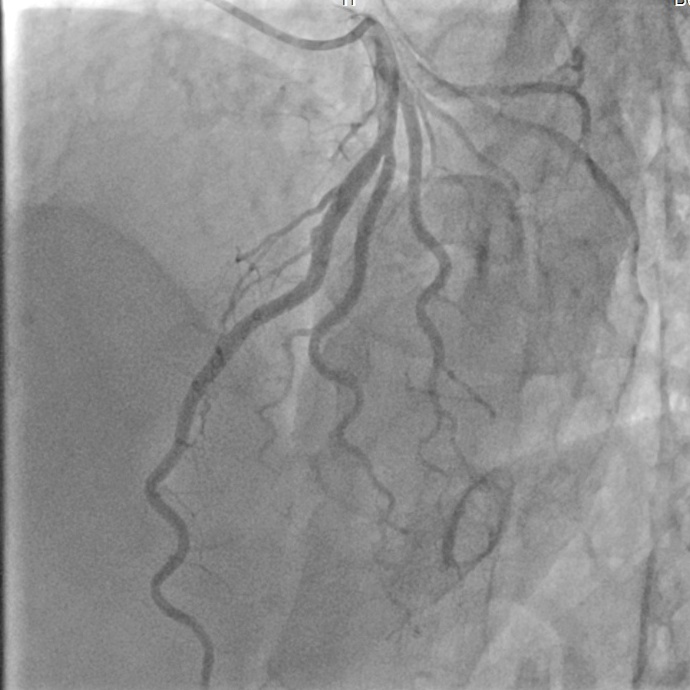

Study with a Real-world Application

Refer to caption

(a) Original Image.

(b) Ground Truth Label.

(c) By Centralized Model.

(d) By Model trained with 333 Workers.

Figure 7: Segmentation Results with U-Net on HEART-VESSEL.

We further studied the performance of the proposed framework, FedPC, with a real-world application used at the School of Medicine, Tan Tao University. The application is also an image segmentation problem applied to heart vessels. The dataset includes 454545 heart vessel images, stored in 333 different locations. We deployed our framework with 333 workers at the three storage locations. The experimental results show that the centralized training approach achieves a segmentation accuracy of 0.92140.92140.9214 while the model trained with the distributed approach with 333 workers approximates the performance with an accuracy of 0.92100.92100.9210. For illustration, in Figure 7, we present the segmentation results obtained by different models and refer to the segmentation obtained by the clinician. We can see that the segmentation obtained by the models trained with FedPC is almost the same as the ground truth label (i.e., segmentation performed by the clinician).